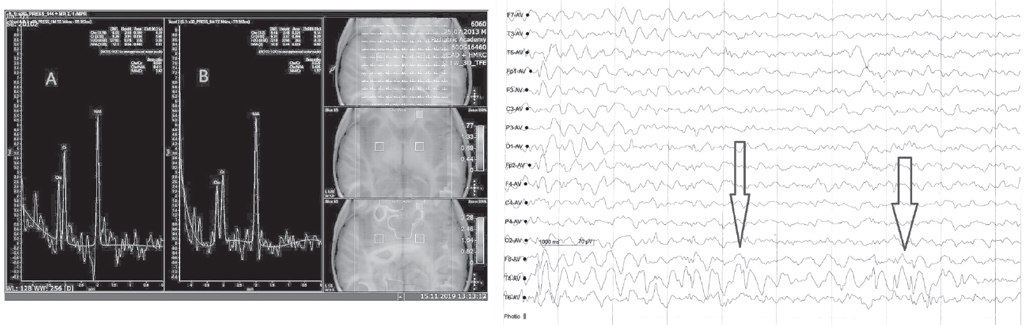

Figure 1 shows the results of changes in the concentration of the main metabolites characteristic of patients with PSDR associated with focal temporal lobe epilepsy. Two patients with PSDR associated with temporal lobe epilepsy, who had a lipid peak on the side of the lesion, showed certain changes in the main metabolites (Fig. 2).

Fig. 1. Left: 1H-MRC of the brain of a patient with mental and speech development delay associated with focal temporal lobe epilepsy. Field of study: poles of the temporal lobes. There is a lateralization of pathology in the right temporal lobe in the form of a decrease in the concentration of N-acetylaspartate (A). The indicators of metabolites in the left temporal lobe are within normal values (B). Right: this patient’s EEG revealed epileptiform activity in the temporal region on the right (arrows), without generalization

Рис. 1. Слева: протонная магнитно-резонансная спектроскопия головного мозга пациента с задержкой психоречевого развития, ассоциированной с фокальной височной эпилепсией. Область исследования: полюсы височных долей. Отмечается латерализация патологии в правой височной доле в виде снижения концентрации N-ацетиласпартата (А). Показатели метаболитов в левой височной доле в пределах нормальных величин (B). Справа: на электроэнцефалограмме выявлена эпилептиформная активность в височной области справа (стрелки), без генерализации